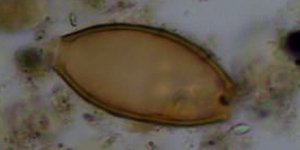

ΚΟΣΜΟΣ 15/12/2017 10:47 Βρήκαν στην Τζια τα παρασιτικά σκουλήκια του Ιπποκράτη, σε αρχαία κόπρανα [εικόνες]